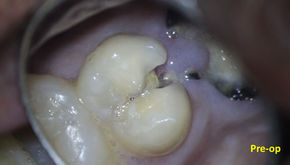

Crack tooth syndrome and MB2

Upper premolar endo and Emax crown